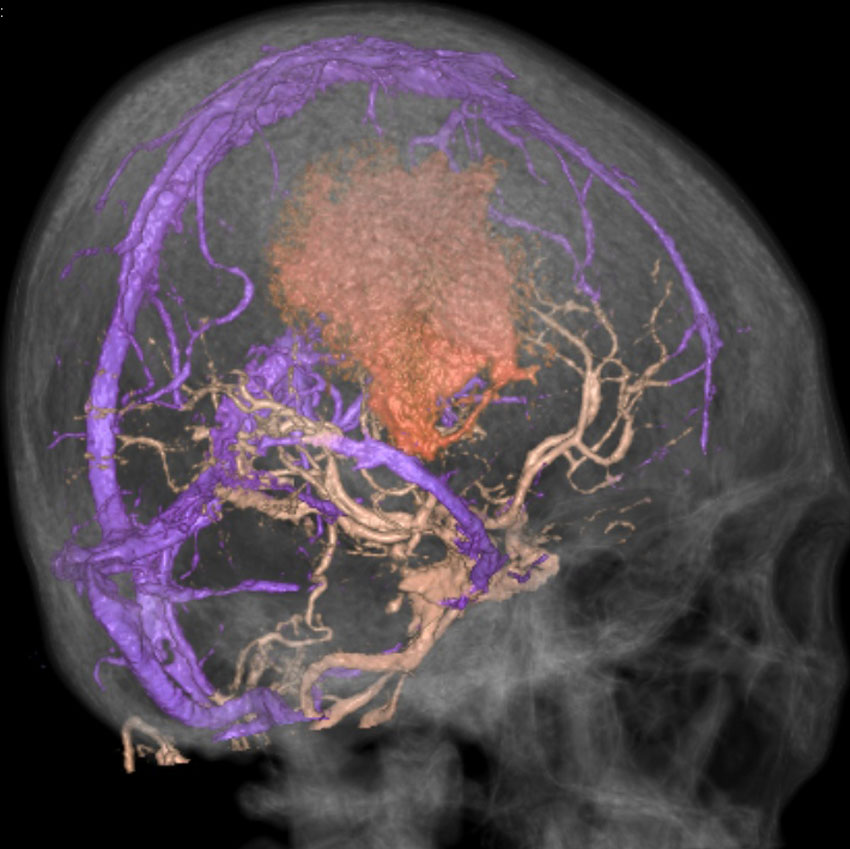

静脈洞交会髄膜腫 meningioma of the confluence of sinuses

若い女性に偶然発見されたものです。直静脈洞と静脈洞交会の接合部あたりに発生したもので,静脈洞はほぼ閉塞に近い所見でした。しかし,この部分の静脈洞は,テント硬静脈側副路が発達することがあるので,硬膜を含めた積極的な摘出をすることは絶対にできません。もしほんの少しでも流れがある直静脈洞を閉塞させると短時間に脳死になるような脳静脈圧亢進が生じる可能性があるからです。静脈洞内に少し取り残して(右下の矢印)手術を終了しました。手術後には定位放射線治療を行って再増大を防ぎます,